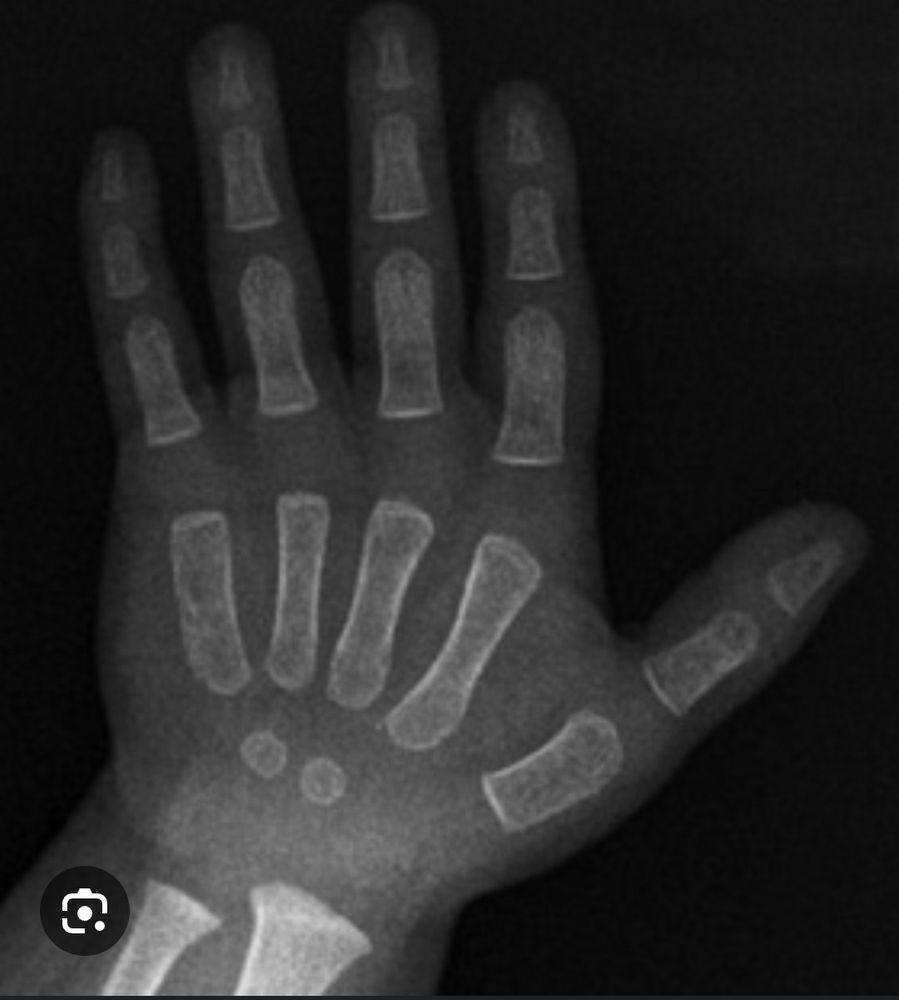

La prueba en si (que si se realiza a todo menor cuando entra) se llama edad osea, los huesos de la mano y muñeca se desarrollan en distintas etapas de la niñez